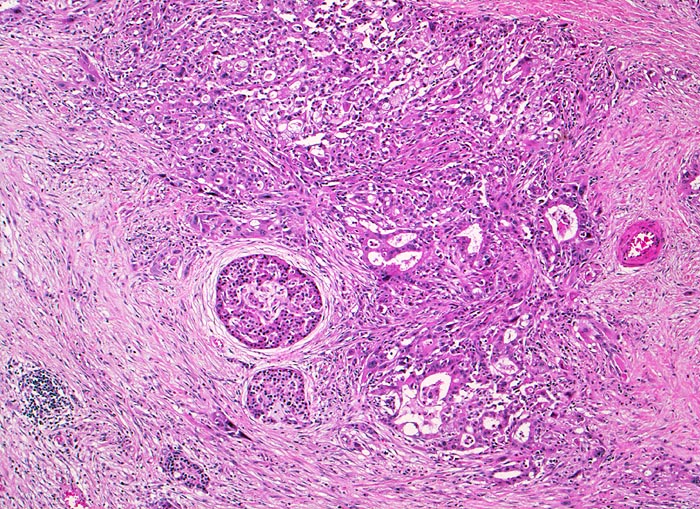

Kleindrüsiges Tumorinfiltrat. Angrenzend an das Tumorinfiltrat ausgeprägte Fibrose (harter Tumor!) mit lockerem Entzündungsinfiltrat und einzelne erhaltene Pankreasinseln.

Unscharf begrenzter weisser derber Herd im Pankreaskopfbereich. Stenosierung und praestenotische Dilatation von Ductus choledochus und Pankreasgang vor der Papille.